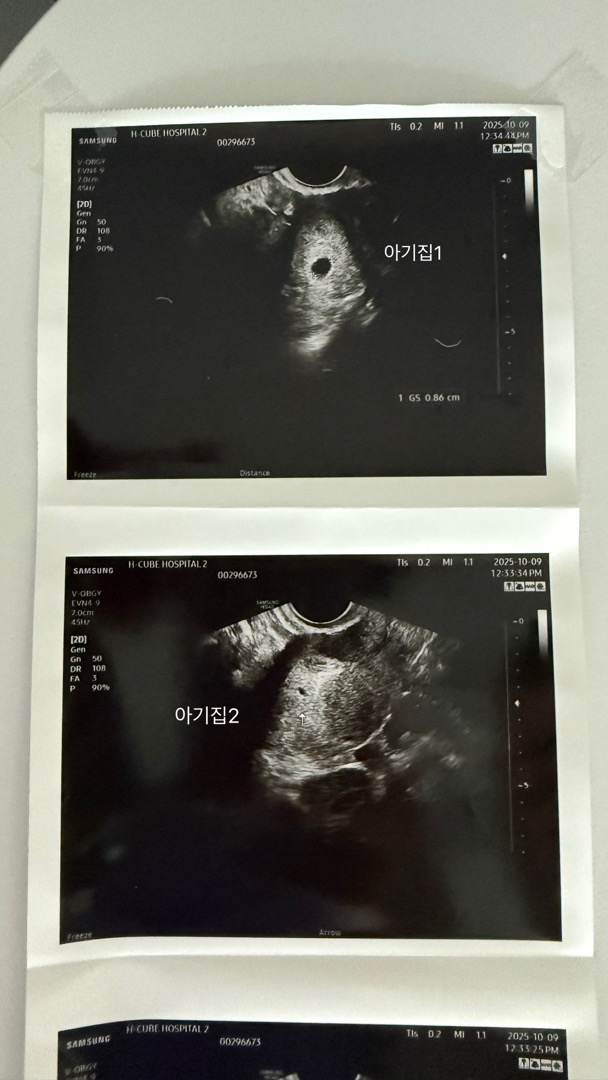

4주6일 병원 첫방문 아기집이 두개가 보인대요

남편이랑 계획하고 시도했는데 다음날 아침 저에게 코인이 대박나는 꿈을 꿨는데 돈으로 안받고 2층 커다란 집을 받았다고 예사롭지 않다며 생생하다길래 저는 복권을 사보자 했는데 아기집이 두개였네요. 자연임신인데 가족력없는 귀한 쌍둥이라니!! 아직 하나가 너무 작고 도태될수도, 예쁘게 살아남을수도 있다기에 열심히 기다려보려구요. 걱정이되어서 2주뒤에 다시 오라고 하셨는데 모든게 괜찮고 난황도 심장소리도 듣고 오고 싶어요!!ㅠㅡㅠ 저같은 분들 계실까요~?